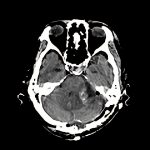

後頭蓋窩髄膜腫

断層撮影

手術前1

No.’13_100 手術前1